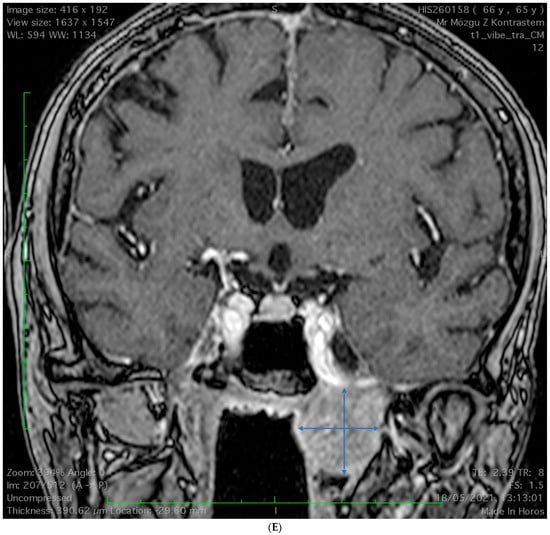

2.1. Case 1